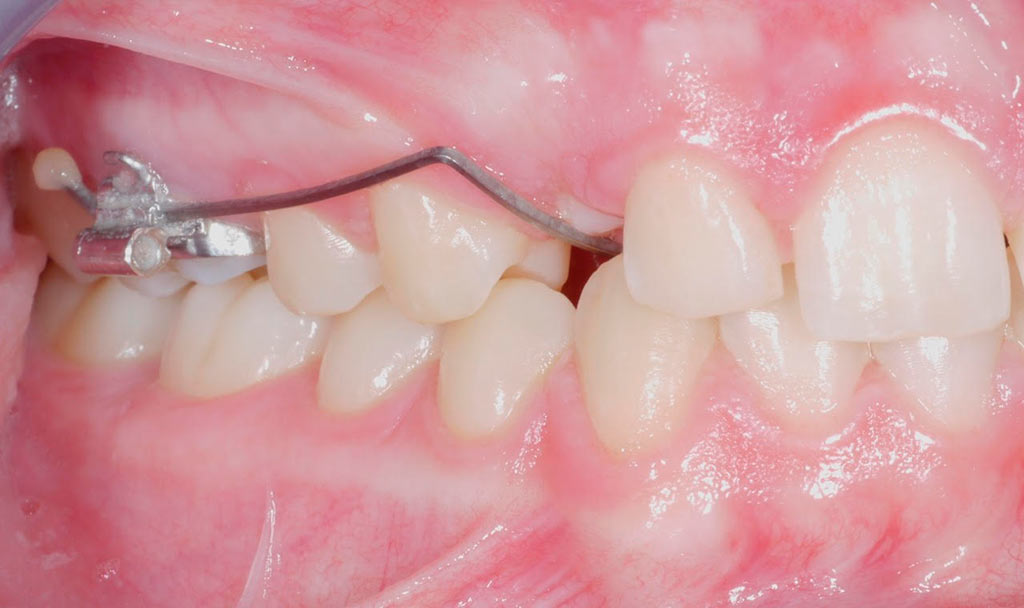

Tracción de canino con k9